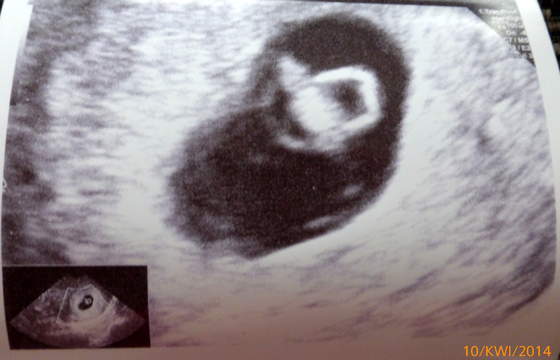

przyjęła mnie nie o 15:15, a po 17, ale najważniejsze, że przyjęła

mam 6,5 cm szczęście, które się prawidłowo rozwija i serduszko mu bije :-)